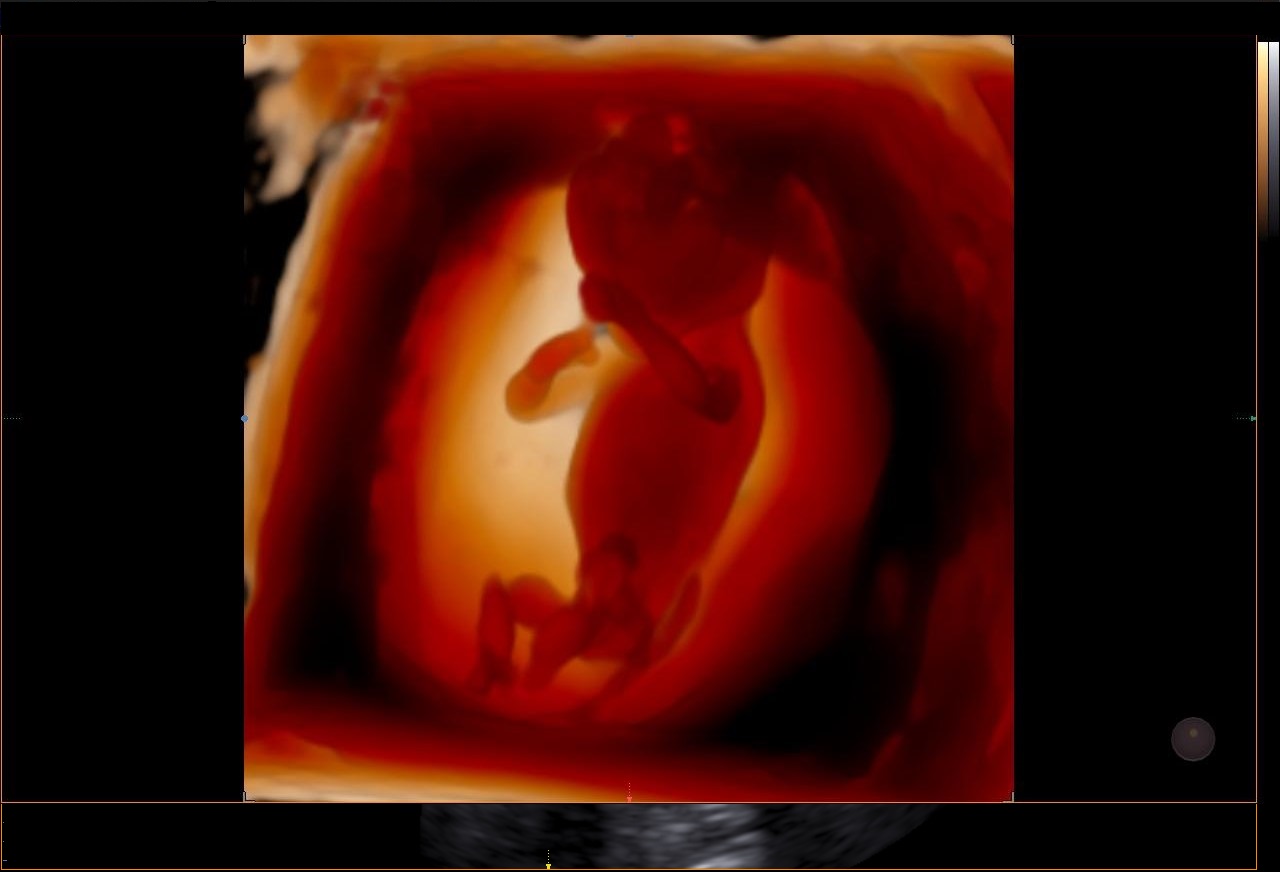

Le RealisticVue™ propose des rendus anatomiques de haute résolution en 3D/4D. Une source lumineuse est modélisée afin de permettre un effet d'ombre sur les structures et de surligner les zones d'intérêt.